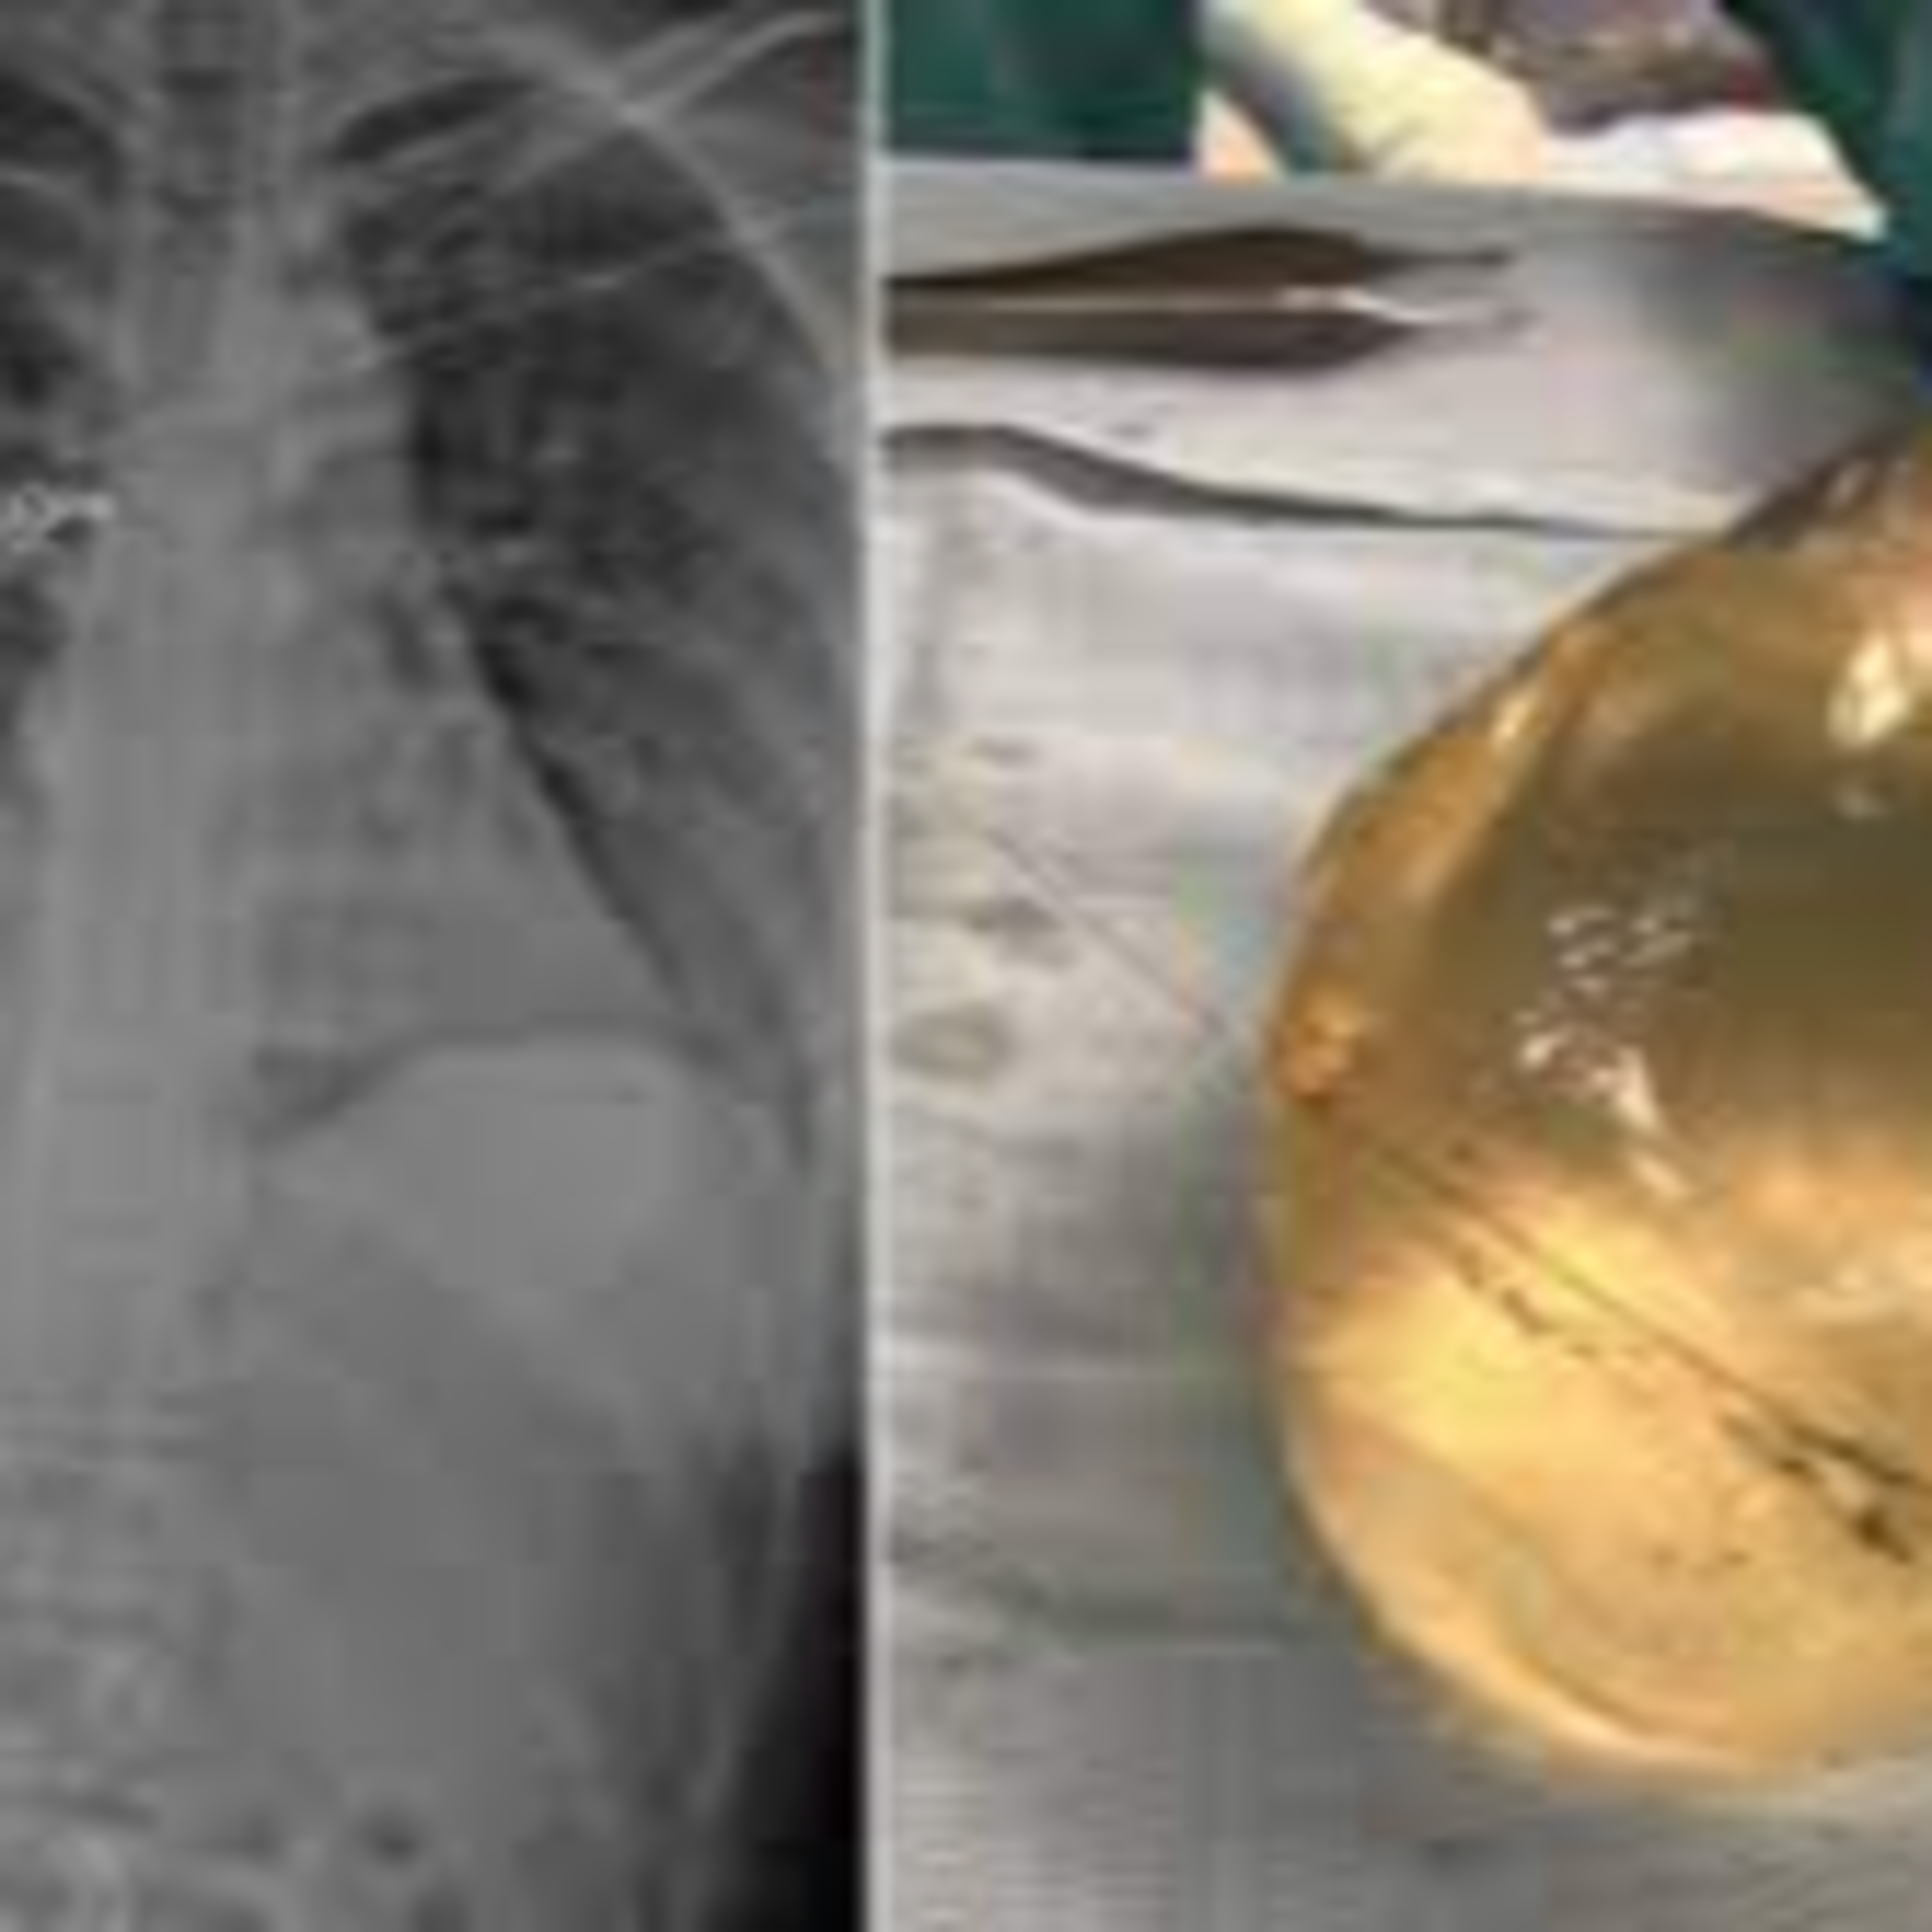

Using trauma radiographs, medics have been capable to spot the bullet in the proper lateral thoracic wall, a fractured rib and air bubbles in the left breast, and concluded that the bullet traveled from the left breast to the proper thoracic wall.

"The bullet wound entry was once on the left breast, however the rib fracture used to be on the proper side. The bullet entered the pores and skin on the left aspect first, and then ricocheted throughout her sternum into the proper breast and broke her rib on the proper side," he explained.

The lady suffered a gunshot wound, damaged ribs and broken implants, however in any other case used to be remarkably unscathed.